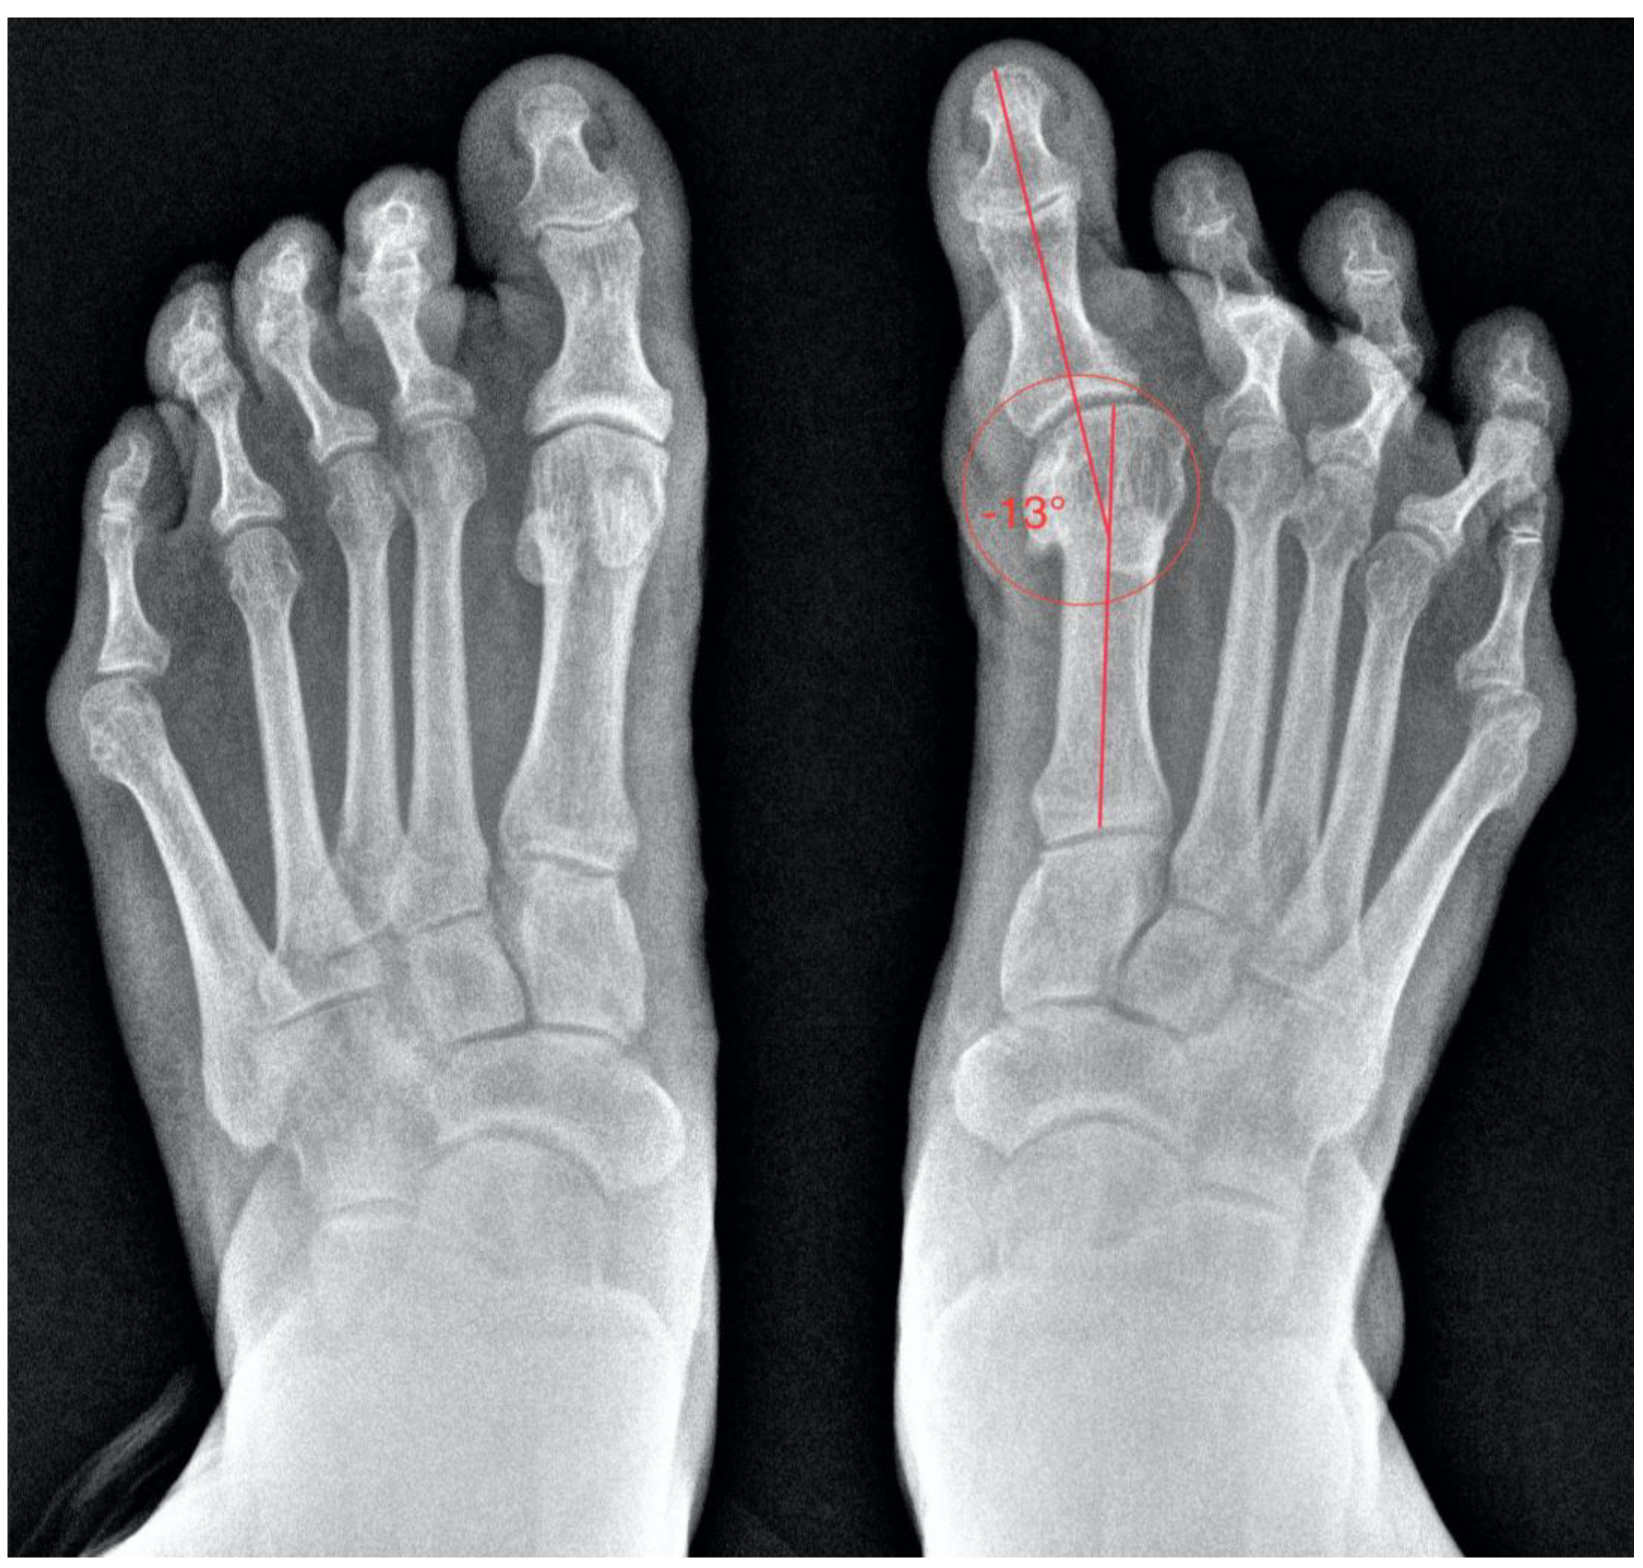

Finally, the radiological study aids in assessing the degree of deformity and the condition of the joints (Figure 2). It also provides insight into the surgical techniques previously employed. It is likely that her prior surgery involved a Silver exostectomy technique combined with soft tissue release, which contributed to the current condition of the toe. Evidence of a Silver exostectomy is also observed on the fifth metatarsal head.

Figure 2.

Preoperative anteroposterior (AP) weight-bearing radiograph of both feet demonstrating significant hallux varus deformity and associated structural abnormalities in the lesser toes.

Hallux varus is an uncommon deformity defined as the medial deviation of the hallux at the metatarsophalangeal (MTP) joint [3]. Radiologically, it is characterized by a negative MTP joint angle. Although rare, hallux varus can result from iatrogenic causes, particularly overcorrection during hallux valgus surgery, with reported incidences ranging from 2% to 15% [4]. The deformity can also arise due to traumatic, post-surgical, inflammatory, or congenital factors. The primary pathophysiology involves an imbalance of muscle-tendon forces, notably between the flexor hallucis brevis and the sesamoid ligaments [5]. Excessive soft tissue release during surgery, including lateral capsule and sesamoid excision, exacerbates this imbalance [6].

Hallux varus presents as a cosmetic deformity or difficulty in shoe fitting, with less frequent complaints of pain [7]. Clinical evaluation focuses on the flexibility of the deformity and associated issues, such as clawing of the lesser toes or compensatory hindfoot supination [8]. Radiographic analysis confirms the diagnosis and evaluates the deformities, commonly identifying a zero or negative MTP angle along with additional structural abnormalities, such as arthritic changes or length discrepancies [9].